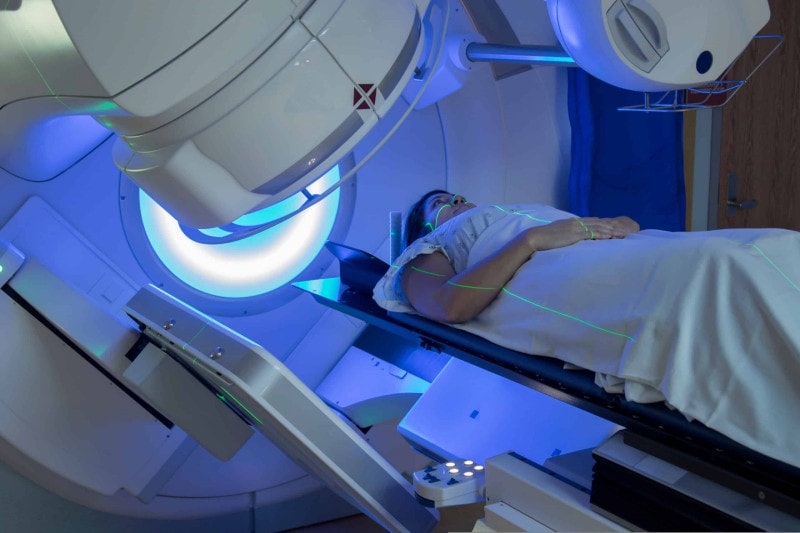

ผู้ป่วยมะเร็งปอดระยะที่ 1-3 ที่ยังไม่พบการกระจายไปยังต่อมน้ำเหลืองภายในช่องอกฝั่งตรงข้ามหรือต่อมน้ำเหลืองเหนือไหปลาร้า ซึ่งรักษาหลักเป็นการผ่าตัดและตามด้วยยาเคมีบำบัดในบางกรณี หากภายหลังการผ่าตัดพบว่ามีการกระจายไปยังต่อมน้ำเหลือง mediastinum หรือผ่าตัดมะเร็งออกได้ไม่หมด แนะนำการฉายรังสีภายหลังการผ่าตัดร่วมด้วย โดยฉายรังสี 27-30 ครั้ง ด้วยการ ฉายรังสี ปรับความเข้มหมุนรอบตัว (VMAT) มักจำลองการฉายรังสีเอกซเรย์คอมพิวเตอร์ (CT simulation) ชนิด 4 มิติ (4D-CT simulation)

ทั้งนี้ผู้ป่วยระยะที่ 3 บางรายอาจได้รับยาเคมีบำบัดหรือการฉายรังสีร่วมกับการให้ยาเคมีบำบัดก่อนการผ่าตัดเพื่อก้อนมีขนาดเล็กลง โดยฉายรังสี 25-30 ครั้ง ด้วยการฉายรังสีปรับความเข้มหมุนรอบตัว (VMAT) ความเข้มรังสี มักจำลองการฉายรังสี 4D-CT Simulation

ส่วนผู้ป่วยระยะที่ 1 ที่ไม่มีการกระจายไปยังต่อมน้ำเหลืองแต่มีปัญหาสุขภาพทำให้ไม่สามารถผ่าตัดได้ การรักษาหลักคือการฉายรังสีร่วมพิกัดทดแทนการผ่าตัด (Stereotactic body radiotherapy, SBRT หรือ Stereotactic ablative radiotherapy, SABR) ฉายรังสีทั้งหมด 3-10 ครั้ง โดยปริมาณรังสีต่อครั้งมากกว่าการฉายรังสีมาตรฐาน มักจำลองการฉายรังสี 4D-CT simulation และมีการตรวจสอบตำแหน่งก่อนฉายรังสีจริงทุกครั้ง

ส่วนกรณีผู้ป่วยระยะที่ 3 ที่มีการกระจายไปยังต่อมน้ำเหลืองภายในช่องอกฝั่งตรงข้ามหรือต่อมน้ำเหลืองเหนือไหปลาร้า ใช้วิธีการรักษาหลักคือการฉายรังสีร่วมกับยาเคมีบำบัดและยาภูมิคุ้มกันบำบัด ฉายรังสี 30-35ครั้ง ด้วยการฉายรังสีปรับความเข้มหมุนรอบตัว (VMAT) มักจำลองการฉายรังสี 4D-CT simulation

สำหรับผู้ป่วยระยะที่ 4 การรักษาหลักคือ systemic treatment ได้แก่ ยาเคมีบำบัด, ยามุ่งเป้า หรือ Immunotherapy และมีการฉายรังสีเพื่อลดอาการของโรคจากมะเร็งบริเวณทรวงอกและตำแหน่งที่มีการแพร่กระจาย โดยทั่วไปฉายรังสีจำนวน 5-10 ครั้ง วันละครั้งต่อเนื่องทุกวัน

ผู้ป่วยระยะที่ 1-3 การรักษาหลักคือการฉายรังสีร่วมกับยาเคมีบำบัด ฉายรังสีจำนวน 30 ครั้ง วันละ 2 ครั้งหรือฉายรังสีวันละครั้งด้วยการฉายรังสีปรับความเข้มหมุนรอบตัว (VMAT) รังสีมักจำลองการฉายรังสี 4D-CT simulation, การฉายรังสีบริเวณสมองเพื่อป้องกันไม่ให้มีการกระจายมะเร็งไปสมอง ฉายรังสี 10 ครั้ง วันละครั้ง มักฉายแบบสามมิติทั่วไป

ผู้ป่วยระยะที่ 4 การรักษาหลักคือ systemic treatment ได้แก่ ยาเคมีบำบัดและยาภูมิคุ้มกันบำบัด กรณีผู้ป่วยที่มีการตอบสนองต่อยาเคมีบำบัดดี อาจพิจารณาฉายรังสีป้องกันมะเร็งกระจายไปบริเวณสมอง และฉายรังสีที่ก้อนที่หลงเหลือบริเวณทรวงอก โดยฉาย 10 ครั้ง มักฉายแบบสามมิติทั่วไป นอกจากนี้จะมีการฉายรังสีบริเวณที่มีการแพร่กระจายของโรค 5-10 ครั้ง เพื่อลดอาการจากมะเร็ง